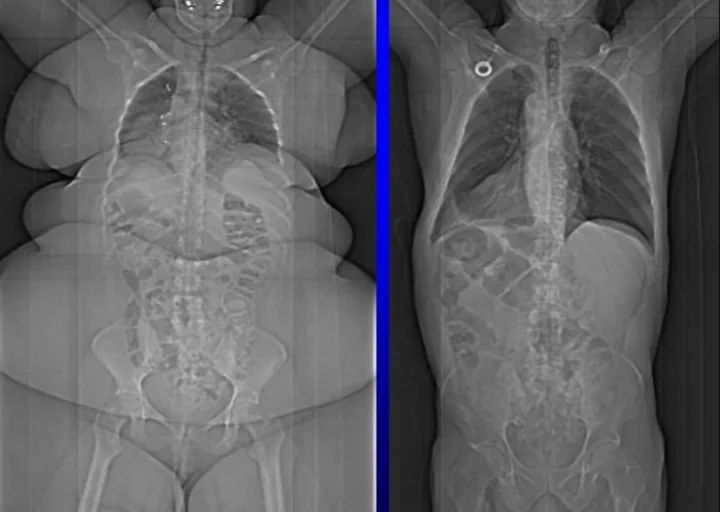

skinny person x-rays compared to overweight persons